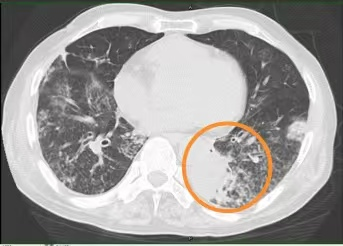

没想到2个月前,王大爷突然开始喘息、气促、胸闷,甚至走几步路都觉得很累,不得不停下休息,慢慢地生活不能自理,连吃饭也没胃口,体重下降。3周前咳嗽、咯痰更重了,咯的全是黄稠痰。在当地医院住院,胸部CT提示:左肺下叶炎症并部分肺实变、右肺中叶部分支气管扩张,经抗感染、吸氧等治疗后一点没缓解。